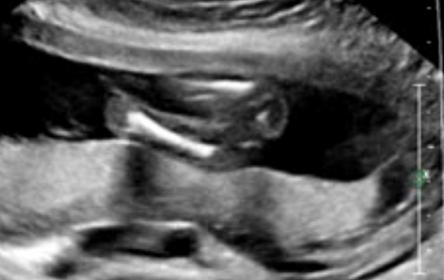

Update! I went yesterday and was 17 weeks 4 days. Tech said she thinks its a girl, but baby closed its legs tight at the end when she checked for gender. When she was measuring the femur, I didn't see anything between legs. Any guesses? Thanks

Attachment 18761